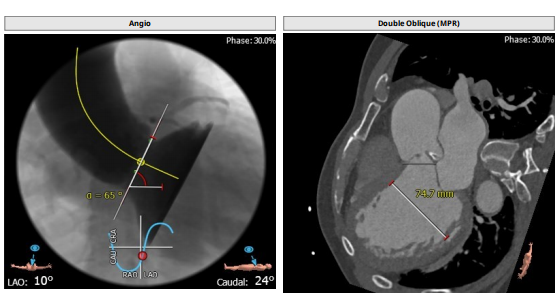

这名AS患者是解剖呈两边大中间小的沙漏形状,即流出道33-34,瓣上结构是左右融合的TYPE1二叶瓣,重度钙化,最窄的地方是瓣上6-8mm,然后STJ有43左右,升主动脉有48左右,再加上65°的横位心,使用自膨瓣膜挑战很大。策略上首选32号瓣膜,但是如何放好是个问题,瓣上type1的瓣叶很难提供足够的锚定力,所以瓣中瓣也是必须要考虑的备选策略。如果考虑球扩瓣,最大只有29号,对于这种超大瓣环也不是最安全的选择,有瓣膜移位的风险。所以可回收的自彭瓣还是较安全,而且可以有多次机会调整,寻找最佳锚定点,实在不行就瓣中瓣,也是一种可以接受的结果。

此例病人Type1二叶瓣,左右冠瓣融合,右无疑似融合,重度钙化,瓣环30.5,LVOT33.9,左右冠高度为16.9mm与18.8mm,右无融合离对侧28-30左右,STJ43.7,升主47.9,整体结构极大,心脏角度65度,近乎横位。